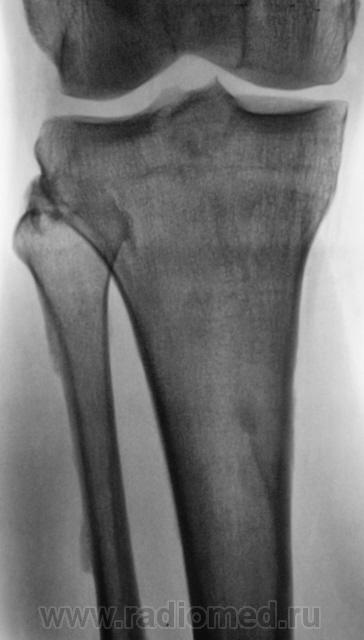

Мужчина средних лет, крепкий, ведущий активный образ жизни, занимающийся дозировано «элементами спорта», полковник милиции, в последнее время (несколько лет) почувствовал боли в области правого коленного сустава.

Снимки ниже.

Энтезопатия надколенника, перегрузочная болезнь б/б кости(подозрение на неполный перелом).

Очень похожая картина на консолидированный перелом б\б кости. В проекции м\б кости определяется периостальная реакция или патологическая перестройка костной ткани.

Есть  признаки  артроза  и  синовита . Была  повреждена  передняя  крестообразная  связка.